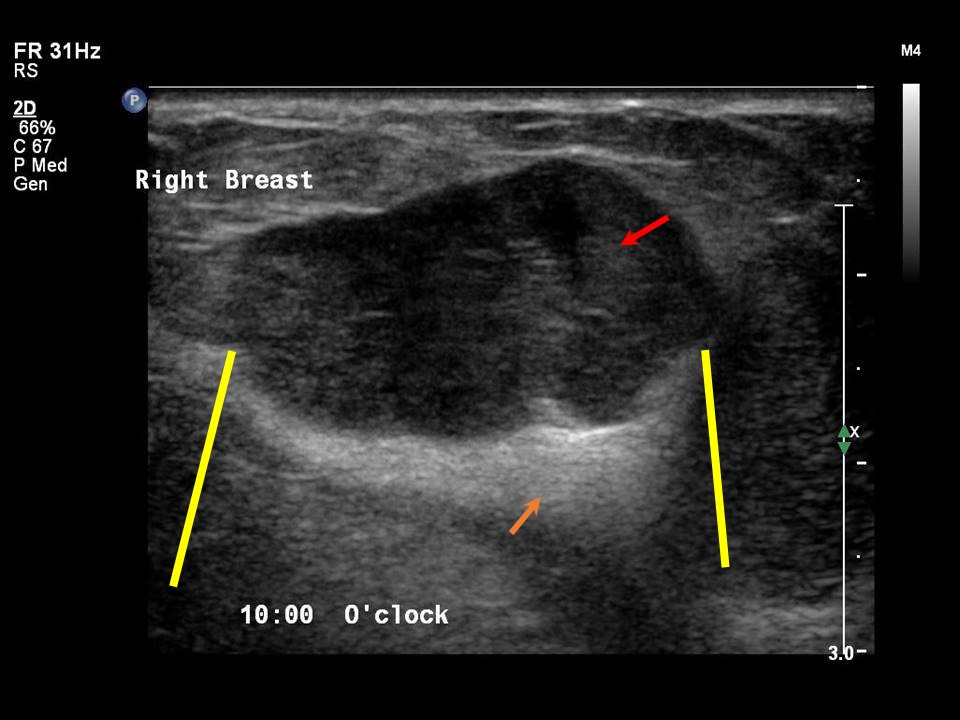

Breast Ultrasound cancer 1 YouTube What Does Shadowing Mean On Breast Ultrasound When silicone leaks out of the implant it will cause a. 30% multiple projections from the nodule within or around ducts. This loss is displayed in the image as. Sometimes this lobulation can give the impression of a lump in the breast (figure). As ultrasonic beams propagate through tissues, there is a loss of energy by absorption, reflection and scattering.. What Does Shadowing Mean On Breast Ultrasound.

Right breast ultrasound demonstrates an irregular shaped, hypoechoic What Does Shadowing Mean On Breast Ultrasound When silicone leaks out of the implant it will cause a. As ultrasonic beams propagate through tissues, there is a loss of energy by absorption, reflection and scattering. 30% multiple projections from the nodule within or around ducts. Acoustic shadowing occurs when an ultrasound beam encounters a highly reflective or dense structure within the body. Collections or silicone leakage **.. What Does Shadowing Mean On Breast Ultrasound.